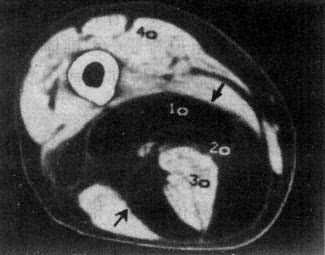

软组织肿瘤的密度一般低于正常肌肉,增强扫描可增加病变和正常肌肉的密度差,多数良性肿瘤边界清楚或有包膜且质地均匀,但定性诊断有一定限度。脂肪瘤因有典型的脂肪密度,表现具有特征性(图2-2-1)。海绵状血管瘤于肿块内可见小圆形静脉石,且在造影增强扫描后,肿瘤明显强化,具有一定的特点。

大腿脂肪瘤

图2-2-1 大腿脂肪瘤

右大腿中1/3后内侧低密度肿块,境界清楚,CT值-100Hu